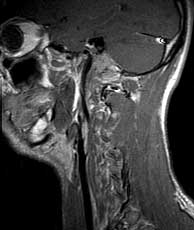

T1 sag post